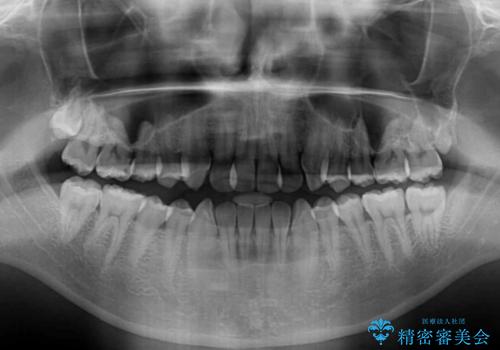

- 前歯のデコボコを気にして来院された患者様です。

歯列としてはワイヤー装置でもインビザラインでも対応可能でしたが、インビザラインが苦手とする上顎側切歯(真ん中から2番目の歯)の舌側転位が顕著でした。

治療の確実性を上げるために、インビザライン開始前に上顎のワイヤー装置にて舌側転位を解消し、その後インビザラインにて矯正治療を行うこととしました。